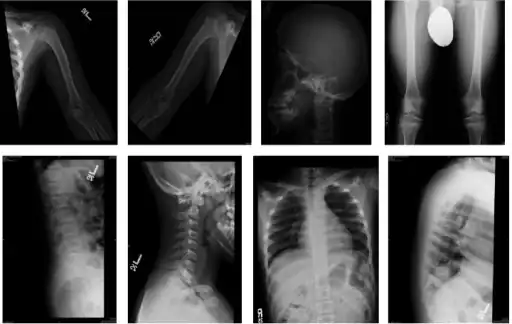

-

Skeletal survey in favor of hypochondroplasia -

The diagnosis of this condition can be done via X-rays (with lack of normal distance L1 to L5),[8] and additionally genetic testing is available to ascertain hypochondroplasia.[9]

However, the physical characteristics are one of the most important in determining the condition.[3]